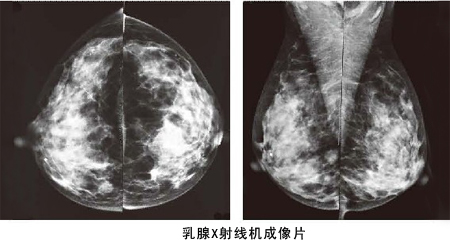

乳腺鉬鈀檢查系統(tǒng)

乳腺鉬鈀檢查系統(tǒng)是目前診斷乳腺疾病的首要選擇和極簡(jiǎn)便、極為可靠的無(wú)創(chuàng)性檢測(cè)手段,痛苦相對(duì)較小,簡(jiǎn)便易行,且分辨率高,重復(fù)性好,留取的圖像可供前后對(duì)比,不受年齡、體形的限制,目前已作為常規(guī)的檢查。

它的特點(diǎn)是可以檢測(cè)出醫(yī)生觸摸不到的乳腺腫塊,特別是對(duì)于大乳房和脂肪型乳房,其診斷性可高達(dá)95%,對(duì)于以少許微小鈣化為獨(dú)有表現(xiàn)的T0期乳腺癌(臨床捫診陰性),也只有憑借軟X線(xiàn)檢查才能被早期發(fā)現(xiàn)和診斷。對(duì)乳腺癌的診斷敏感性為82%~89%,特異性為87%~94%,是目前所有輔助檢查中陽(yáng)性率較高的。

為什么被稱(chēng)為早期診斷的金標(biāo)準(zhǔn)?

乳腺鉬靶X線(xiàn)片不同于普通X線(xiàn)片,普通X線(xiàn)片對(duì)乳房中正常組織與腫塊影的鑒別能力很差,而乳腺鉬靶X線(xiàn)片能精細(xì)地記錄下不同穿透能力的軟組織留下的X線(xiàn)影像,特別是能捕捉到對(duì)乳腺癌具有診斷意義的微小鈣化灶。臨床應(yīng)用證實(shí),它能發(fā)現(xiàn)小于5mm的癌腫,可以至少比臨床提前1年發(fā)現(xiàn)乳腺癌。

乳腺鉬鈀檢查系統(tǒng)成像

乳腺鉬鈀檢查系統(tǒng)具有乳腺斷層攝影技術(shù)、乳腺對(duì)比增強(qiáng)技術(shù)、立體定位活檢技術(shù),合三為一,貫穿乳腺篩查、診斷、治療全路徑,更準(zhǔn)確、清晰的成像,更早發(fā)現(xiàn)乳腺癌微小病變,為乳腺癌早期發(fā)現(xiàn)、早期診斷以及治療和術(shù)后監(jiān)控全流程帶來(lái)完整的解決方案,被作為目前全球范圍內(nèi)乳腺影像檢查的“金標(biāo)準(zhǔn)”。